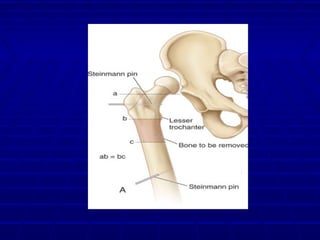

Derotational femoral shorteningDerotational femoral shortening

osteotomyosteotomy

Femoral osteotomyFemoral osteotomy

 Schoenecker + Strecker 1984Schoenecker + Strecker 1984

 Traction vs. Femoral shorteningTraction vs. Femoral shortening

 56% AVN in traction group56% AVN in traction group

 0% AVN in femoral shortening0% AVN in femoral shortening